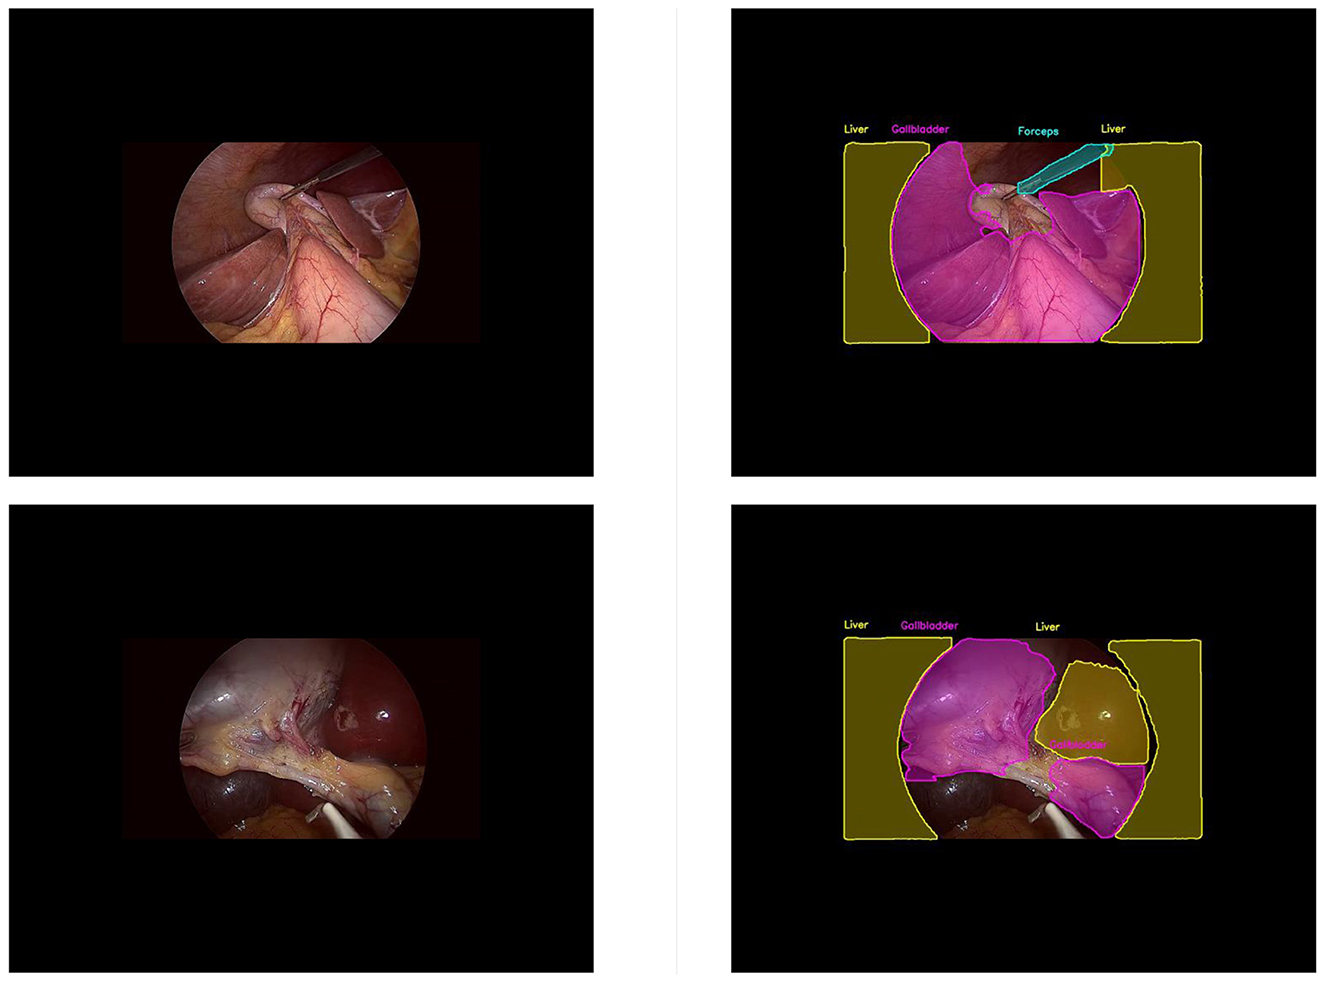

LC-YOLOmatch: A Novel Scene Segmentation Approach Based on YOLO for Laparoscopic Cholecystectomy

Laparoscopy is a visual biosensor that can obtain real-time images of the body cavity, assisting in minimally invasive surgery. Laparoscopic cholecystectomy is one of the most frequently performed endoscopic surgeries and the most fundamental modular surgery. However, many iatrogenic complications still occur each year, mainly due to the anatomical recognition errors of the surgeons. Therefore, the development of artificial intelligence-assisted recognition is of great significance. This paper proposes a method based on the lightweight YOLOv11n model. By introducing the efficient multi-scale feature extraction module DWR, the real-time performance of the model is enhanced. Additionally, the bidirectional feature pyramid network (BiFPN) is incorporated to strengthen the capability of multi-scale feature fusion. Finally, we developed the LC-YOLOmatch semi-supervised learning framework, which effectively addresses the issue of scarce labeled data in the medical field. The experimental results on the publicly available Cholec80 dataset show that this method achieves 70% mAP50 and 40.8% mAP50-95, reaching a new technical level and reducing the reliance on manual annotations. These improvements not only highlight its potential in automated surgeries but also significantly enhance the assistance in laparoscopic procedures while effectively reducing the incidence of complications.